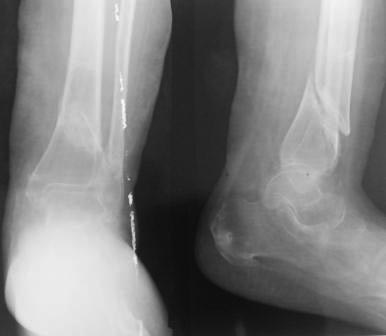

[Ortho] Тугой ложный сустав большеберцовой кости

Госпитализирована женщина 52 года, 9 месяцев назад произведена КДО

аппаратом Илизарова по поводу косого перелома  дистального метадиафиза

костей левой голени,  образовался  тугой ложный сустав.

В плане БИОС реконструктивным стержнем,  уважаемые коллеги какие будут

мнение? ,